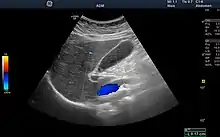

Ultrasound image showing the liver, gallbladder and common bile duct.

Medical ultrasound uses high frequency broadband sound waves in the megahertz range that are reflected by tissue to varying degrees to produce (up to 3D) images. This is commonly associated with imaging the fetus in pregnant women. Uses of ultrasound are much broader, however. Other important uses include imaging the abdominal organs, heart, breast, muscles, tendons, arteries and veins. While it may provide less anatomical detail than techniques such as CT or MRI, it has several advantages which make it ideal in numerous situations, in particular that it studies the function of moving structures in real-time, emits no ionizing radiation, and contains speckle that can be used in elastography. Ultrasound is also used as a popular research tool for capturing raw data, that can be made available through an ultrasound research interface, for the purpose of tissue characterization and implementation of new image processing techniques. The concepts of ultrasound differ from other medical imaging modalities in the fact that it is operated by the transmission and receipt of sound waves. The high frequency sound waves are sent into the tissue and depending on the composition of the different tissues; the signal will be attenuated and returned at separate intervals. A path of reflected sound waves in a multilayered structure can be defined by an input acoustic impedance (ultrasound sound wave) and the Reflection and transmission coefficients of the relative structures.[13] It is very safe to use and does not appear to cause any adverse effects. It is also relatively inexpensive and quick to perform. Ultrasound scanners can be taken to critically ill patients in intensive care units, avoiding the danger caused while moving the patient to the radiology department. The real-time moving image obtained can be used to guide drainage and biopsy procedures. Doppler capabilities on modern scanners allow the blood flow in arteries and veins to be assessed.